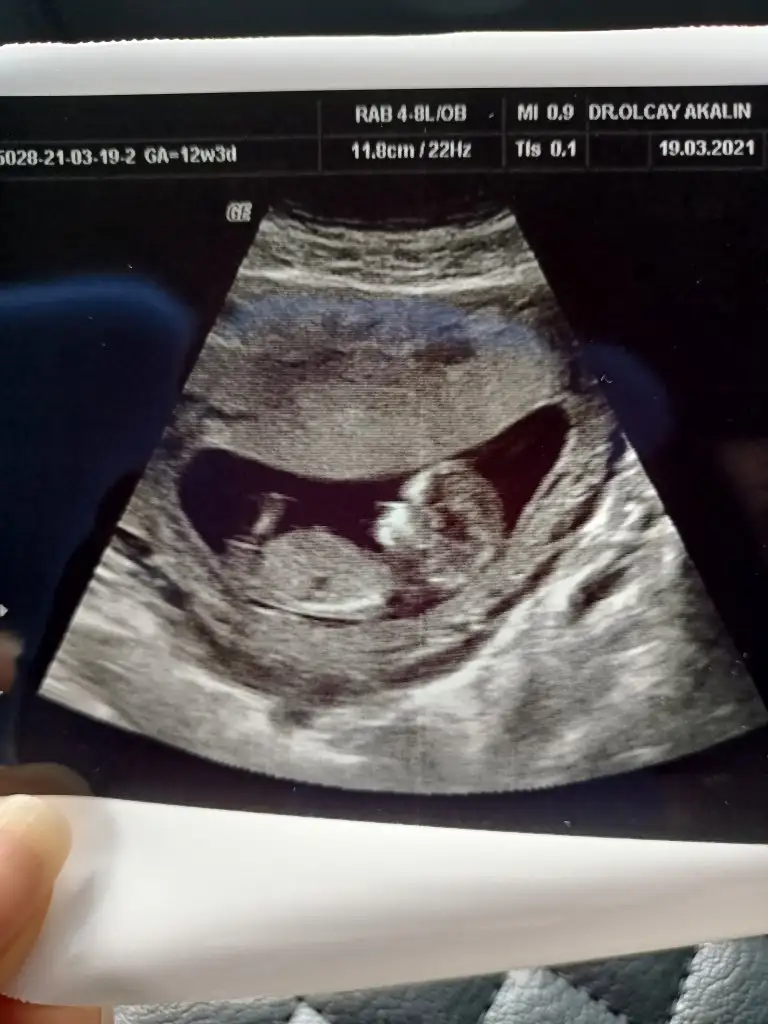

Ikra meyra Ikra meyra tahminin doğru çıktı 16 hafta erkek demiştin doktorum kesin erkek elbiselerini bile al dedi ☺ değişir mi bilmiyorum ama atıyim bir bak

• IMG-20210319-WA0000.webp

IMG-20210319-WA0000.webp

14,5 KB · Görüntüleme: 88

Artık erkektir canım 😍 sağlıkla gelsin oğlusun 🥰 anketim oylarsaniz sevinirim 😘